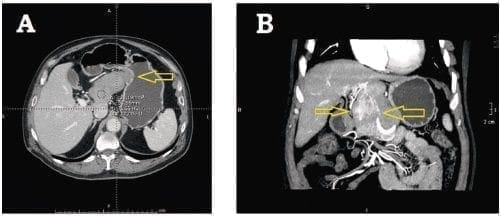

La tomografía computadorizada (TC) de abdomen con administración de contraste intravenoso, demuestra una gran masa hepática hipodensa, heterogénea, muy irrigada y bien delimitada por una cápsula que se intensifica en la fase arterial temprana (30 segundos) (figura 1A) 10,14,15,17,26-30. En la fase portal (1 minuto), se identifican múltiples áreas hipodensas de intensidad variable (figura 1B) 13,15,17,25-27. Durante la fase venosa más tardía (5 minutos), el aumento de la densidad de la tumoración alcanza su máxima expresión 26. Es posible observar áreas de necrosis dentro del tumor y calcificaciones en su cápsula 11,18,20,28, características que podría llevar a diagnosticar el tumor como un quiste hepático con múltiples tabiques 12. Estas imágenes quísticas no se modifican durante todas las fases del estudio 26.

Figura 1. Tomografía abdominal computadorizada. A. Fase arterial temprana en la que se observa un tumor fibroso solitario como una masa hepática hipodensa, heterogénea, muy irrigada, bien definida y delimitada por una cápsula gruesa en un paciente de 58 años de edad. B. Fase portal, en la cual es posible identificar un tumor fibroso solitario del hígado con múltiples áreas hipodensas con diferentes grados de realce.